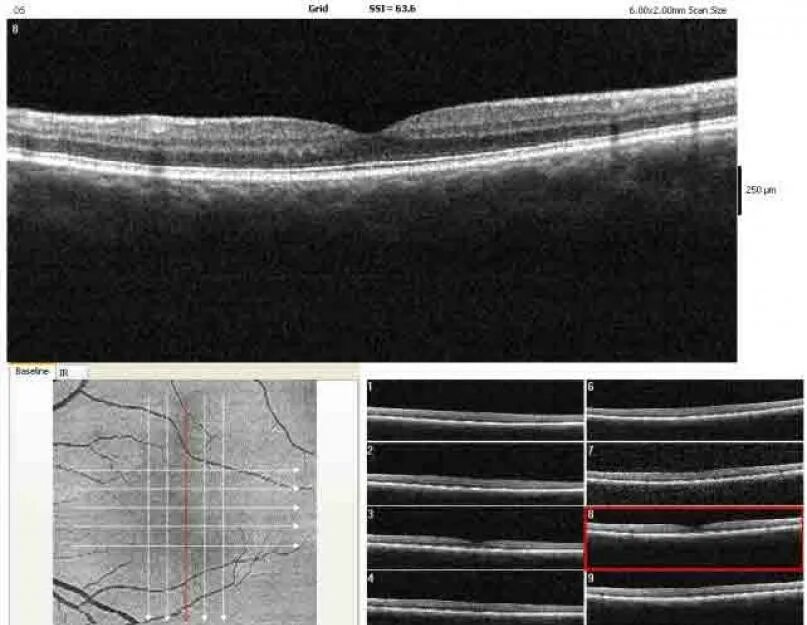

Окт изображение